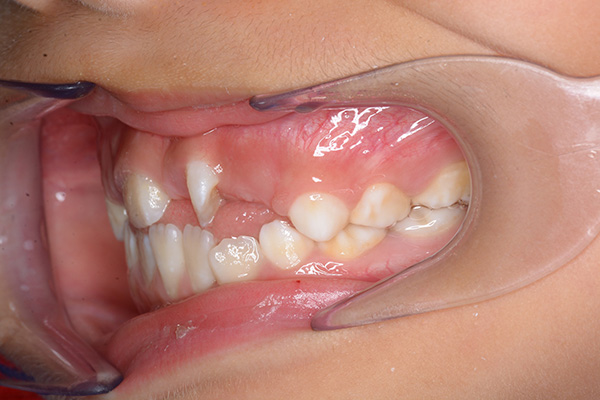

| 主訴 | 上顎前歯のでこぼこ | 診断名 | アングルⅡ級叢生症例 | ||||

|---|---|---|---|---|---|---|---|

| 初診時年齢 | 6歳9ヵ月 | 性別 | 男 | 動的治療期間 | 6ヵ月 | ||

| 既往歴として上顎正中過剰歯(2本)は抜去済み。その影響で上顎右側中切歯は捻転して萌出しており、下顎右側中切歯と早期接触が認められたため2x4(上顎のみブラケット装着)にて前歯部の改善を行った。現在は永久歯列完成まで経過観察を行い、希望があれば口元の突出感を改善するために本格矯正治療を行うことにしている。 | |